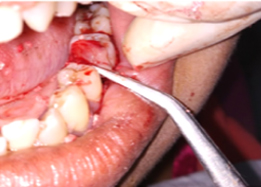

Hemisectomy

Half of Lower molar tooth along with diseased root removed & rest part is saved.

Post-OP Clinical View